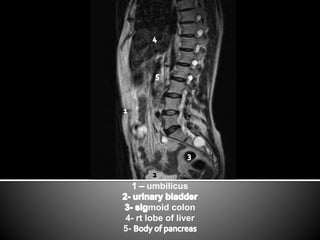

This document lists anatomical structures in the human abdomen including the umbilicus, aorta, skin, subcutaneous fat, sigmoid colon, erector spinae muscles, transverse colon, urinary bladder, right lobe of liver, gall bladder, and pancreas.